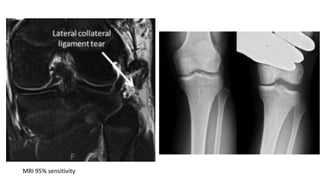

MRI 95% sensitivity

LATERAL COLLATERAL LIGAMENT (FIBULAR

COLLATERAL LIGAMENT)

• Injury to the Lateral Collateral Ligament (LCL) typically occurs due to varus force